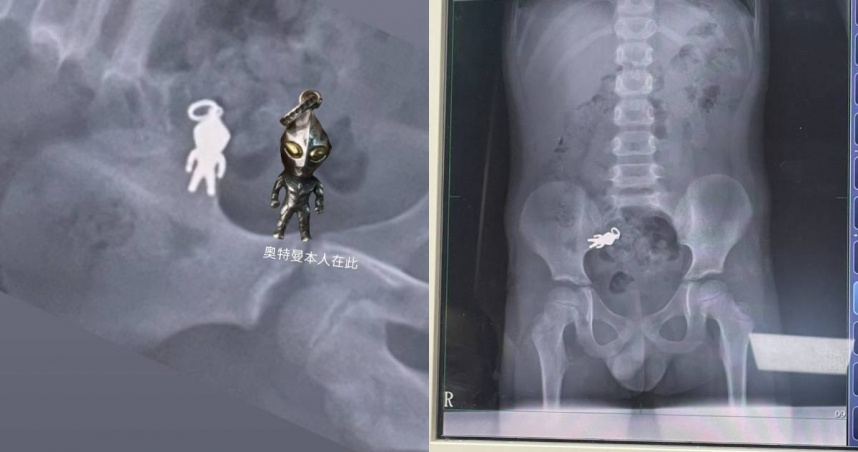

男童誤食奧特曼吊飾。(圖/翻攝Threads/@shushu1011)

宜蘭一名7歲男童上週六在家中一邊看電視、一邊吃餅乾時,不慎將手中的「奧特曼吊飾」吞入腹中,家人發現後緊急帶往羅東博愛醫院就醫。經X光檢查,影像顯示男童腹腔內清楚可見完整人形異物,經醫師評估為吊飾,目前已隨腸道蠕動進入小腸,尚無立即危險。

診治醫師謝錦桐表示,該吊飾尺寸約為2.8公分乘1.4公分,經初步檢查,男童生命徵象穩定,並無不適症狀。醫師建議家屬返家後持續觀察排便情況,若能順利排出即可,不須立即開刀或侵入性處置。